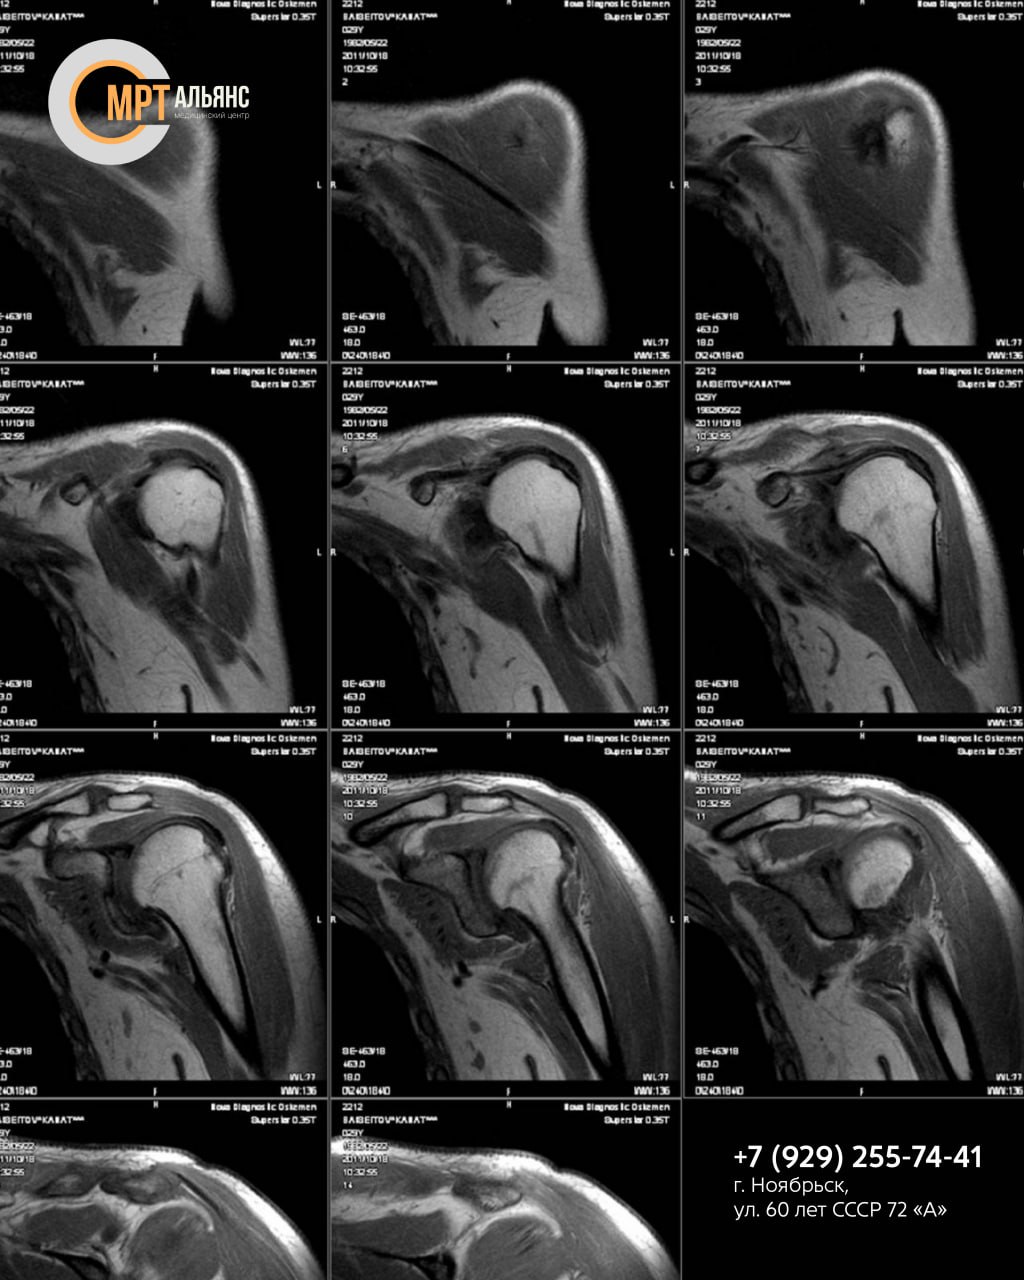

МР-сканирование послойно визуализирует ткани плеча с точностью до 1 мм, оценивая состояние:

• мягких тканей

• сосудов

• костей

• нервных корешков

Выявляем:

• воспаления, опухоли, трещины хрящей

• сдавливание сосудов, травмы, патологии суставов (артрит, тендинит, бурсит и др.)

• скрытые повреждения после ушибов, подвывихов

МР-исследование проводится при подозрении на патологии плеча: инфекционные, аутоиммунные, травматические, воспалительные, некротические, нейропатические и другие